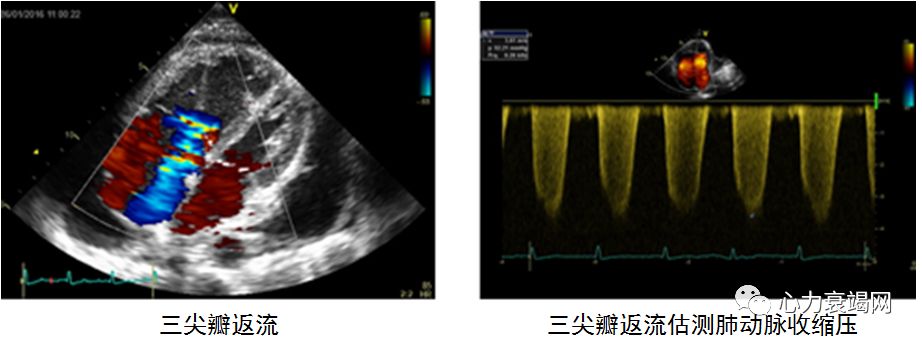

心脏超声:右心房、右心室增大,三尖瓣重度返流,速度4.9m/s,跨三尖瓣压差96mmHg

心脏超声:右心房、右心室增大,三尖瓣轻—中度返流,速度4.3m/s,跨三尖瓣压差76mmHg

➤ 心脏超声

心脏超声是第一步,无创评估右室壁运动不正常,估测肺动脉压力

常用指标

三尖瓣返流速度,>2.7m/s

TDI三尖瓣环收缩期运动速度S’,≤ 9.5 cm/s

TAPSE指数,≤15mm

Tei指数,≥0.55(组织多普勒法),>0.4(多普勒法)

缺点:不能精确评价右室功能,尤其声窗差的患者